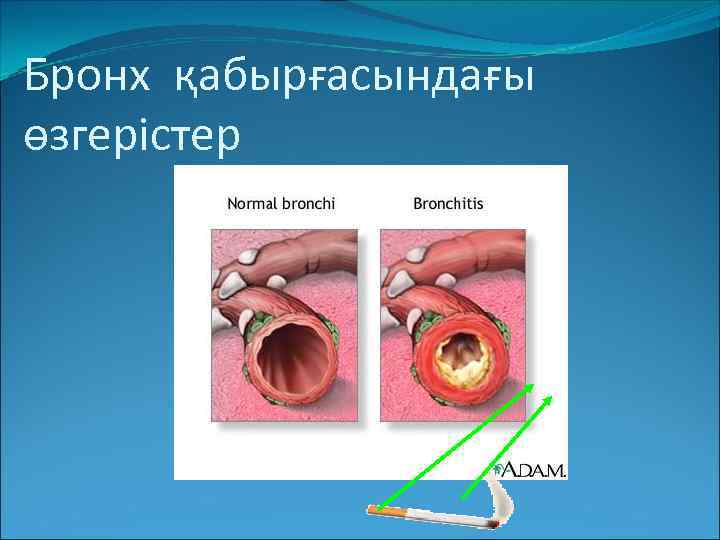

Бронх қабырғасындағы өзгерістер